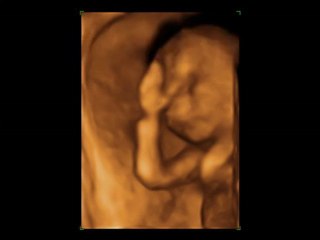

#gebeliktakibi #4Dultrason #ultrason #ultrasonografi #4boyutluultrasonografi #4dultrasonografi br br Ultrasonografinin temel prensibi; yüksek frekanstaki ses dalgalarının hasta üzerine uygulanan prob aracılığı ile doku ve organlara gönderilmesiyle, bu dokulardan yansıyan dalgaların yine aynı prob ile alınarak bir ekran üzerine yansıtılmasıdır. br br Seçilmiş bu frekans ve dalga boyundaki ses dalgaları tamamen güvenlidir ve anneye veya bebeğe kesinlikle zarar vermez. br Normal gebelik takiplerinde erken haftalarda transvajinal, ilerleyen haftalarda da transabdominal yolla anne karnındaki bebek değerlendirilebilir. br Buna doğal olarak doktorunuz karar vermelidir. br br Gebelerin temel ultrasonografik değerlendirmelerinde nelere bakılır? br Fetus (bebek) sayısı br Fetal prezantasyon (bebeğin geliş şekli) br Fetal pozisyon (bebeğin duruş şekli) br Plasental lokasyon (plasenta yerleşimi) br Amniyon sıvı miktarı (bebek kesesindeki su miktarı) br Gestasyonel yaş (gebelik yaşı) br Maternal (annedeki) pelvik kitlelerin teşhis ve değerlendirmesi br Bebeğin gözle görülebilen anatomik yapısı ve olabilecek anormallikler br Bebeğin kordonundaki ve bazı organlarındaki damarlarda kan akım değerlendirmeleri br br Detaylı bilgi ve randevu için, sitelerimizi ziyaret edebilirsiniz br www.meltemhastanesi.